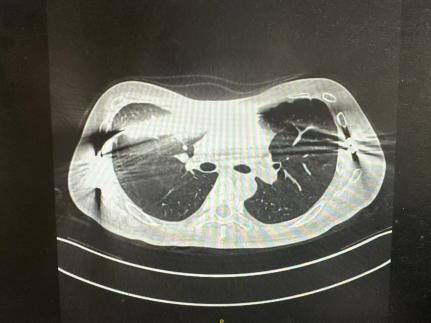

Patient: A 17-year-old adolescent.

Challenge: He had a deep, symmetric pectus excavatum that became more pronounced during his adolescent growth spurt, affecting his posture and willingness to participate in activities like swimming.

Surgical Precision: Despite the severity, detailed CT-based planning indicated that a single, expertly placed and contoured pectus bar would suffice to achieve an ideal lift.

Outcome: The surgery proceeded exactly as planned. The single bar provided perfect, stable correction. The patient healed quickly and was thrilled with his new profile—demonstrating how a targeted, precise approach can deliver life-changing results with maximum efficiency.